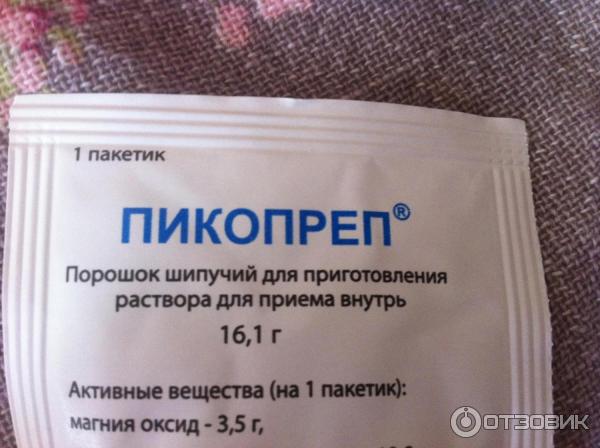

Подготовка к ирригоскопии: необходимые препараты